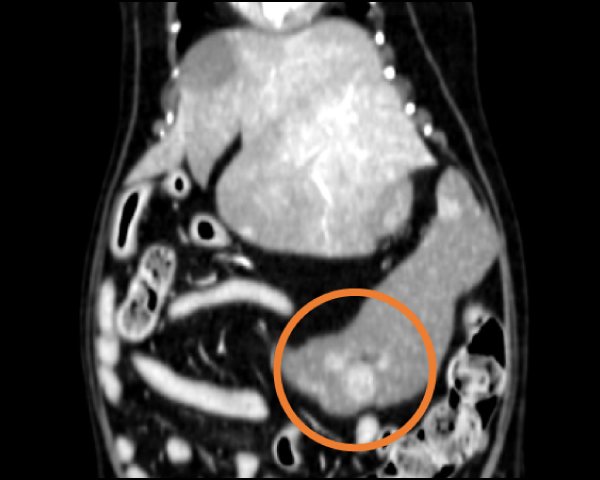

造影CT検査にて腫瘤の浸潤・転移を評価

脾臓の多発性吸収結節像を確認